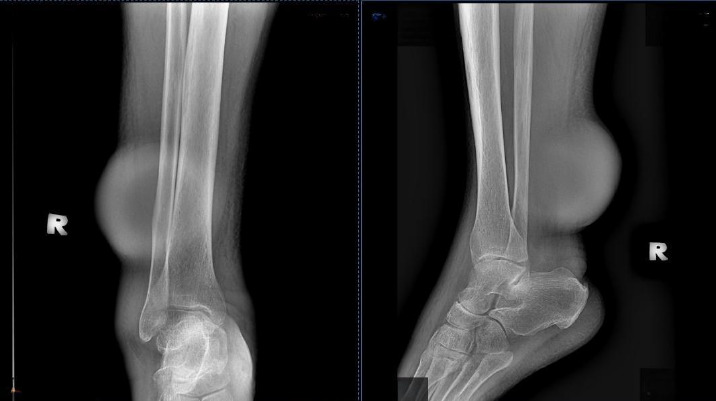

This is a case report of a middle-aged man who presented with chronic unilateral lower limb swelling and a mass on the same side. Several important differential diagnoses were considered. Lymphatic filariasis was included in the differential diagnoses due to a history of travel to a district endemic with filariasis in Sabah. A final diagnosis of soft tissue sarcoma was provisionally made based on the magnetic resonance imaging findings and confirmed by histopathological examination as pleomorphic dermal sarcoma. Both conditions are unusual but important causes in primary care due to their association with poor morbidity and risk of mortality. Patient management should involve a multidisciplinary team, including primary care, public health, radiology, pathology and orthopaedics.